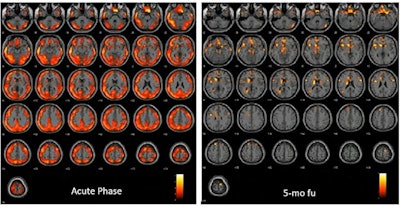

In one patient, FDG-PET during the acute phase showed an extended and severe hypometabolism affecting almost all brain cortices and some subcortical regions (caudates and L-thalamus). At five-month follow-up, only some spots of hypometabolism are present in the superior and middle frontal cortex, superior medial frontal cortex, and L-caudate nucleus. Image courtesy of Anna Lisa Martini.The results demonstrate the following three key points, Martini explained.

Molecular imaging findings in five patients with FDG-PET scans within two months from the infection showed extended orbital, prefrontal, and temporal-parietal cortex hypometabolism. Three patients with FDG-PET scans five months after the SARS-CoV-2 acute phase showed normal brain metabolism and normal cognitive scores.